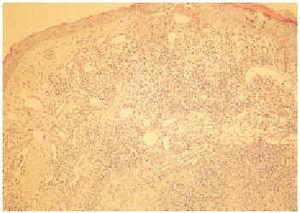

En el estudio histológico se apreció, bajo una epidermis suprayacente adelgazada y ulcerada en algún punto, una proliferación vascular mal definida en la dermis reticular superficial y media acompañada de un denso infiltrado inflamatorio (fig. 2). Esta proliferación estaba constituida por vasos con luces de diámetro variable, de pared fina en la dermis superficial y gruesa en la dermis media. Los endotelios vasculares se componían de células prominentes, con amplios citoplasmas eosinófilos y núcleos vesiculosos, pero no se apreciaban ni pleomorfismo ni mitosis. En algunas zonas de la dermis media la proliferación vascular era muy densa, a modo de cordones celulares de aspecto epitelioide con luces vasculares pequeñas y escasas. El infiltrado inflamatorio que rodeaba a estos vasos se componía predominantemente de linfocitos y de un gran número de eosinófilos (fig. 3).

Fig. 3.--Detalle de las luces vasculares tapizadas por células endoteliales prominentes. La estroma muestra un infiltrado rico en linfocitos y eosinófilos.